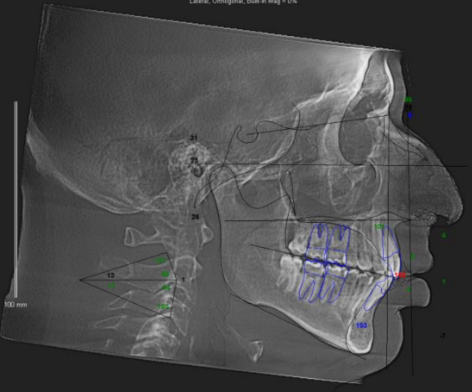

They are planning on doing a segmental 3-piece Lefort 1 which should give me about 5mm of expansion and 8mm of advancement, along with a CCW rotation of a few degrees (my dumbass forgot to ask how many) and a BSSO mandibular advancement of 12mm.

Feel free to ask any questions, also if any autists out there want to make comments about my scans, current appearance and my surgery plans then please do so.